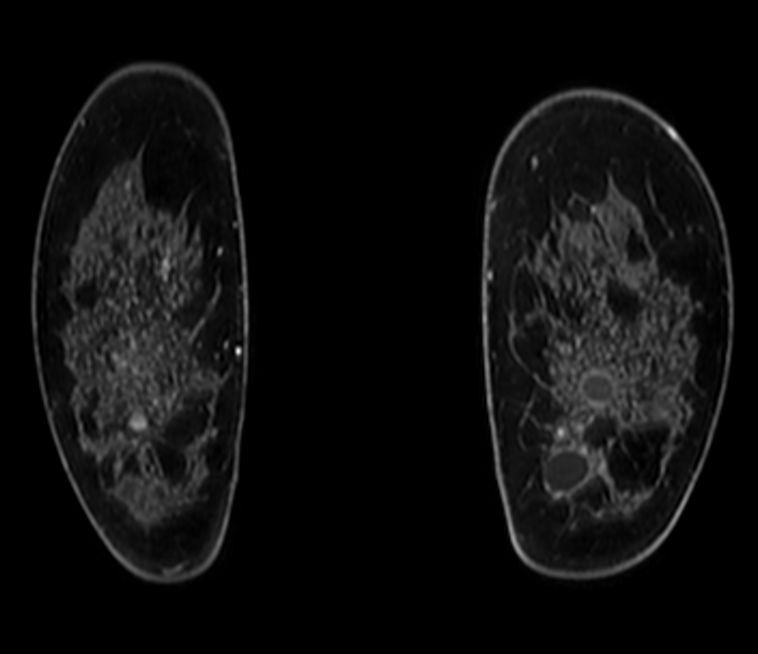

Axial 3D T2w BreastVIEW

Axial 3D VANE XD